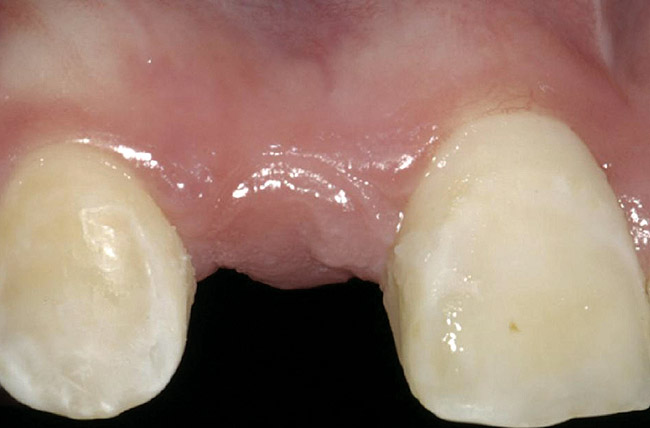

Figure 2  Congenitally missing maxillary right lateral incisor.

Figure 2